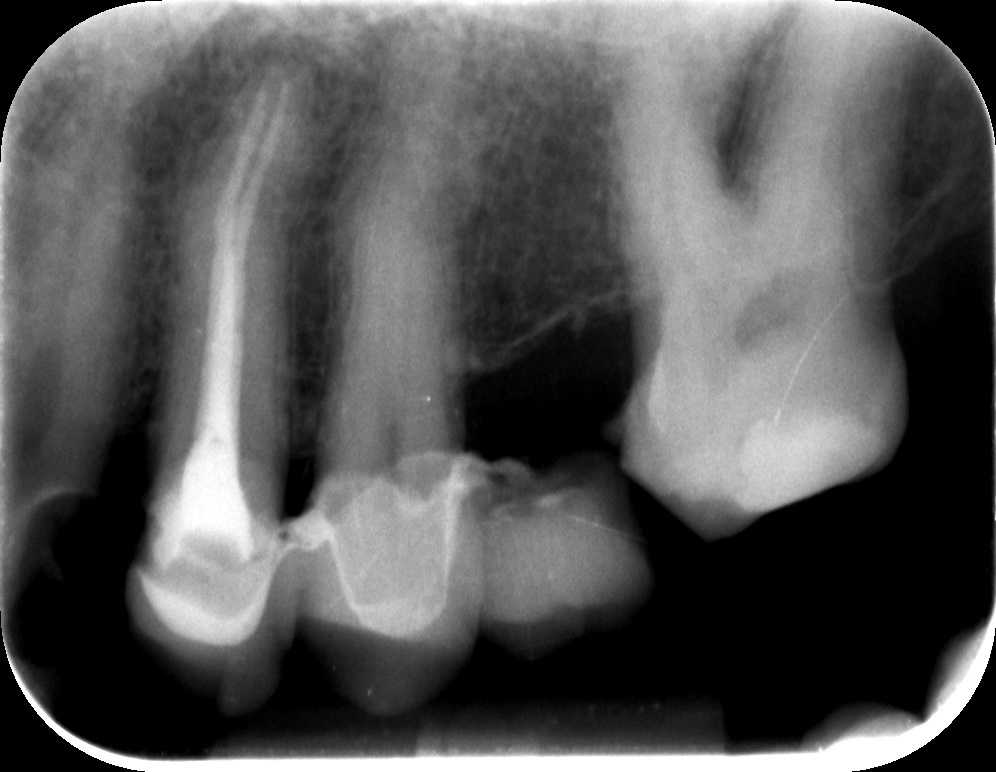

A második alkalommal a csatornák újabb fertőtlenítésére, tisztítására került sor. Ezek után elkészült az új gyökértömés, melyhez ismét igénybe vettük a mikroszkóp segítségét.

A fog panaszmentessé vált – így hát megmenekült attól, hogy el kelljen távolítani!

Egy 3 hónapos kontrollfelvétel után már elkészíthető az új fogpótlás, hogy a páciens mosolya újra olyan legyen, mint régen.